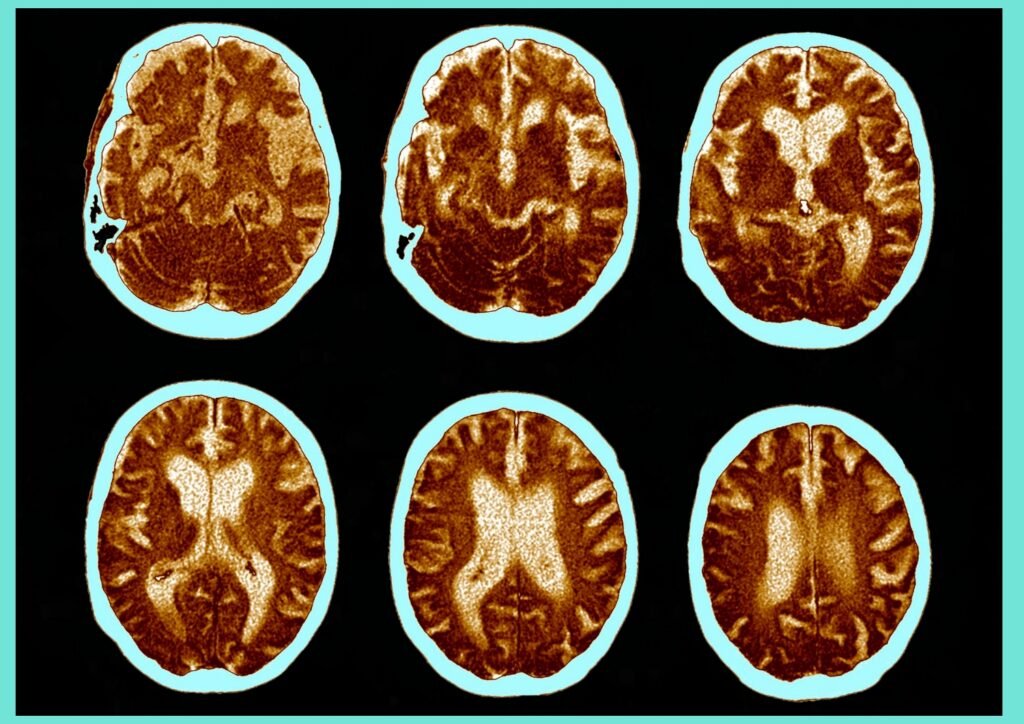

This revolutionary approach uses precisely timed light pulses at 40 flashes per second to stimulate your brain’s natural gamma waves – the same brain rhythms that help you process memories, stay focused, and maintain clear thinking. Recent research from prestigious institutions like MIT has shown that this gentle light stimulation can actually help clear harmful proteins from the brain, potentially slowing the progression of Alzheimer’s disease.

40-Hz therapy operates on a fascinating principle. It essentially increases the flow of cerebrospinal fluid (CSF) into the brain. This fluid movement is like a gentle wave washing over the brain’s surface, picking up unwanted debris such as beta-amyloid proteins, which are linked to Alzheimer’s disease.

40-Hz therapy boosts CSF flow in the brain, helping clear beta-amyloid proteins associated with Alzheimer’s. These proteins are like the waste that clogs the brain’s pathways, and the gamma light therapy for Alzheimer’s helps gather this waste and guide it towards the brain’s natural waste removal channels.